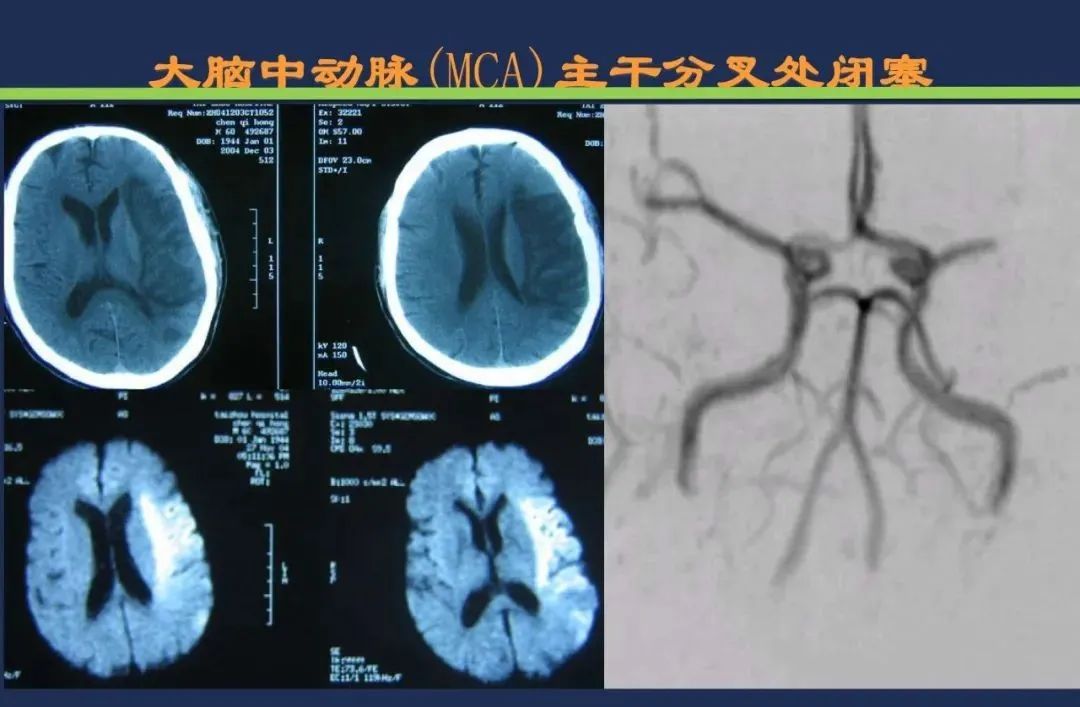

颈内动脉系统梗死颈内动脉大脑中动脉